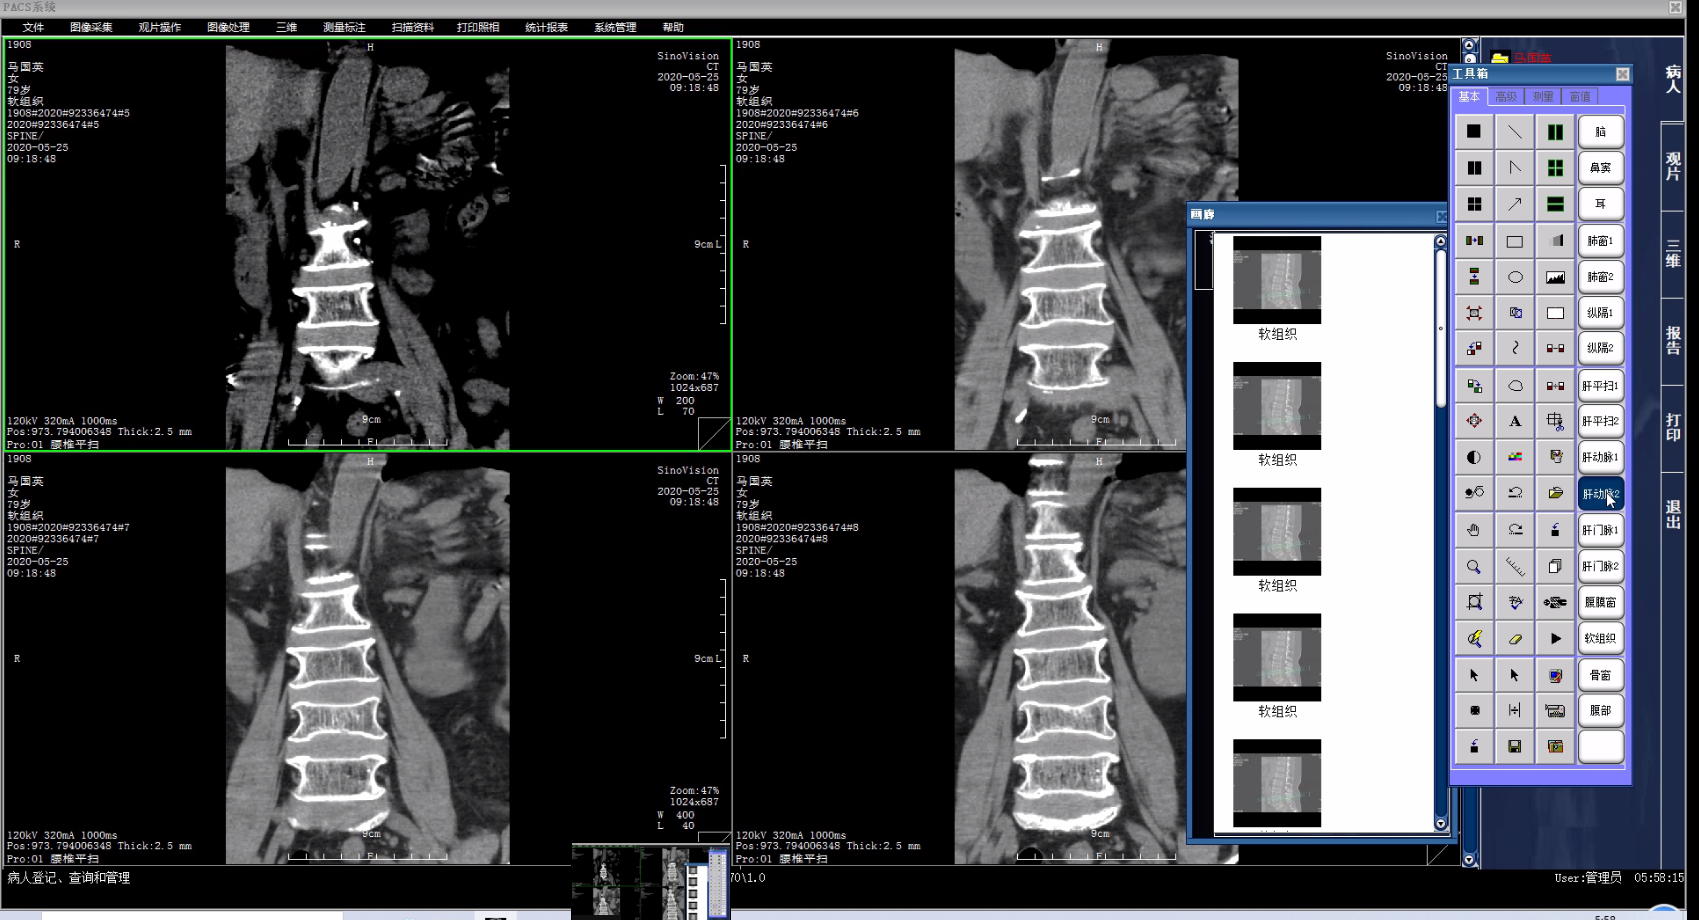

PACS系统核心技术解析:DICOM协议、分级存储与工作流程

PACS系统属于医院信息系统的核心模块之一。该系统整合了放射医学、计算机技术、数字图像处理等技术,用于医疗影像的数字化获取、存储、管理、传输及调阅,替代传统胶片存储方式,提升医疗工作效率。

2、观片工作站

医学影像系统的核心组成部分,由影像医技站调用,是医生用于观片诊断的平台,包括图像观察、图像操作、图像处理、图像标注测量、报告处理、胶片打印(DICOM 打印)及高级影像处理等功能,用于指定病人的图像诊断,也可作为独立的应用系统单独使用。

功能特色

自适应调窗,窗宽、窗位的调整

鼠标穿梭定位

三维鼠标

矢冠状重建

序列间图像同步

自定义观片方式(图像布局和预设窗口)

图像缩放,放大镜功能